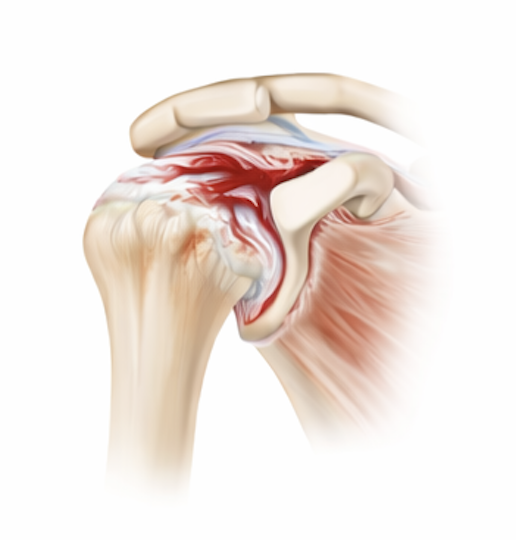

Rotator Cuff Tears